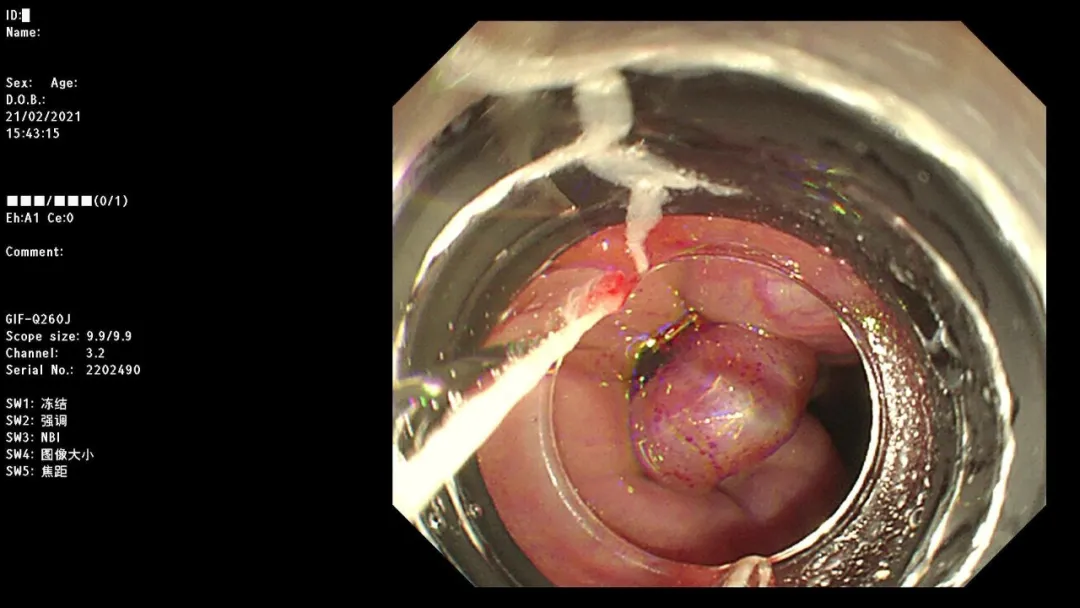

病例二:女,呕血1天,于南大一附院消化科就诊,以“上消化道出血”收治住院。

急诊胃镜示:小弯近胃窦侧活动性出血灶活动性渗血,采用OTSC吻合夹予以夹闭治疗,检查诊断:胃窦杜氏溃疡并出血OTSC吻合夹夹闭止血治疗术。